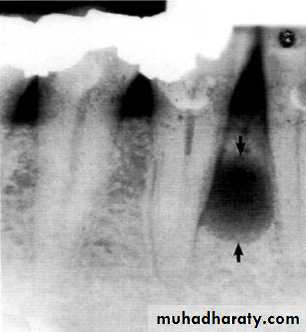

A well-defined lesion is one in which most of the periphery is well defined. If an imaginary pencil can be used to draw confidently the limits of the lesion, the margin is well defined.

Ill-defined periphery difficult to draw an exact delineation around most of lesion.

Well-Defined Borders

1-Punched-Out Border. A punched-out border is one that has a sharp boundary there is no bone reaction apparent immediately adjacent to the abnormality.2-Corticated Border. A corticated margin is a thin, fairly uniform radiopaque line of reactive bone at the periphery of a lesion. This is commonly seen with cysts and benign slow-growing tumors